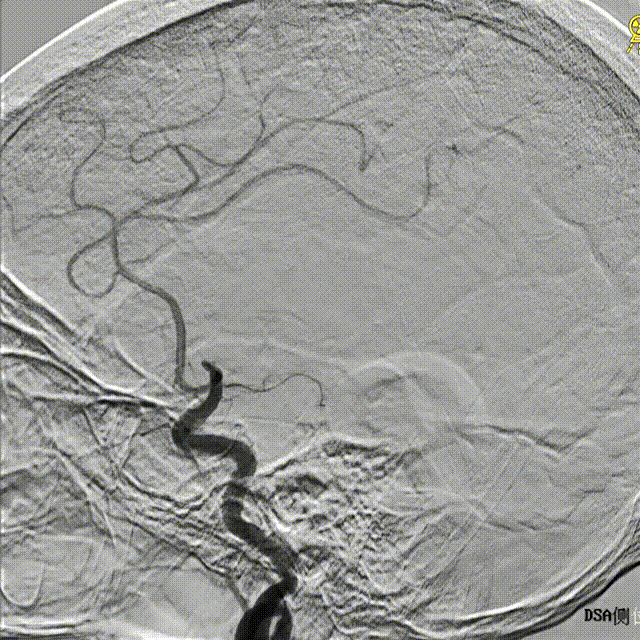

正侧位造影。

正位

侧位